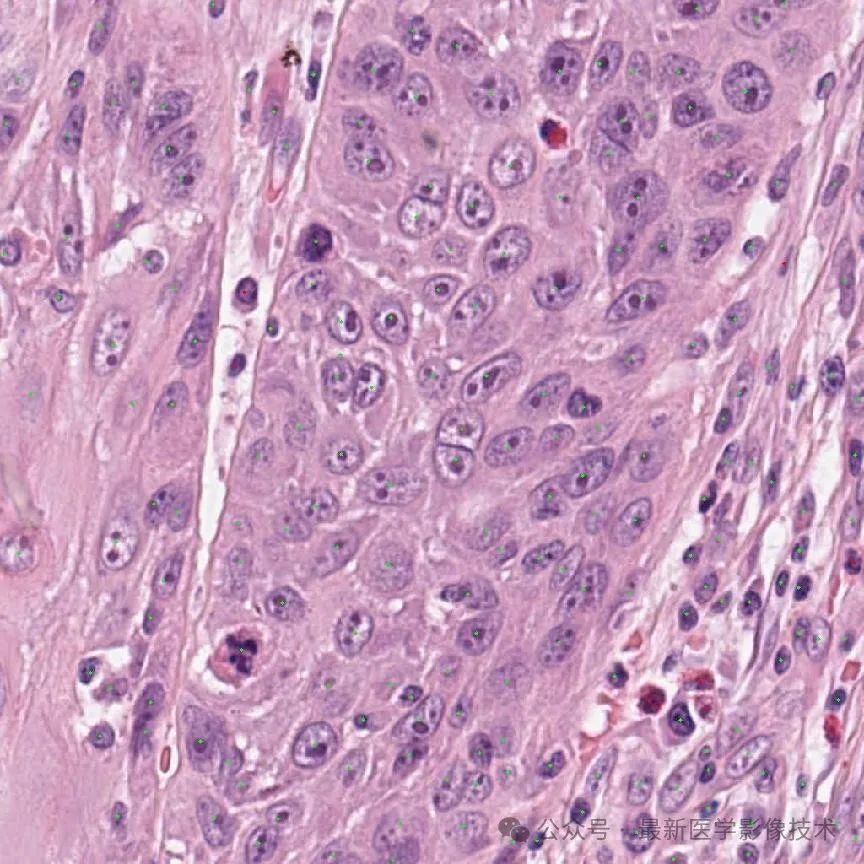

OCELOT 数据集是一个组织病理学数据集,旨在促进利用细胞和组织关系的方法的开发。该数据集由从数字扫描的整个幻灯片图像 (WSI) 中提取的小视场 (FoV) 块和大视场 (FoV) 块组成, 重叠区域。小和大 FoV 斑块分别附有细胞和组织的注释。WSI 源自公开的 TCGA 数据库,并在使用 Aperio 扫描仪扫描之前使用 H&E 方法进行染色。OCELOT数据集的每个样本由六个部分组成,其中x_s,x_l是从WSI中提取的小和大FoV斑块,y_s^c,y_l^t分别指相应的细胞和组织注释,c_x,c_y是x_s中心在x_l内的相对坐标。

下图显示了示例的可视化。

数据集的每个样本都包含两个输入块和相应的注释。左侧显示了带有组织分割注释 y_l^t 的大 FoV 块 x_l,其中绿色表示癌症区域。右侧显示带有细胞点注释 y_s^c 的小视场块 x_s,其中蓝色和黄色点分别表示肿瘤和背景细胞。红色框表示 x_s 相对于 x_l 的大小和位置。请注意,对于每个样本,x_s 和 x_l 是重叠的,即 x_s 存在于 x_l 内部。然而,x_s 在 x_l 上的相对位置因样本而异。

细胞检测任务受益于细粒度的空间信息,可以更好地捕获详细的细胞属性(例如边界、形状、颜色和不透明度)。相比之下,组织分割需要更大的背景才能更好地理解整体结构信息。因此,将x_s(细胞检测)和x_l(组织分割)的FoV大小分别定义为1024×1024和4096×4096像素,分辨率为0.2微米每像素(MPP)。最后,将大 FoV 块和组织注释 (x_l, y_l^t) 下采样4倍,得到1024x1024像素的大小。